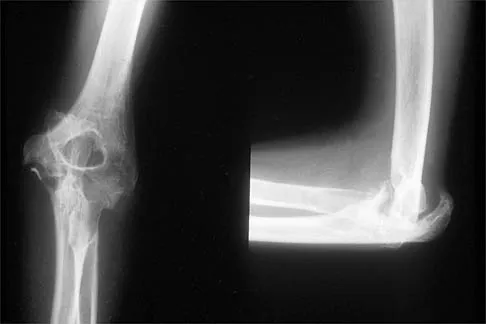

Orthopedic MCQs

Test your knowledge with updated Orthopedic MCQs for 2026. Perfect for board exam preparation, FRCS, and Prometric test practice.